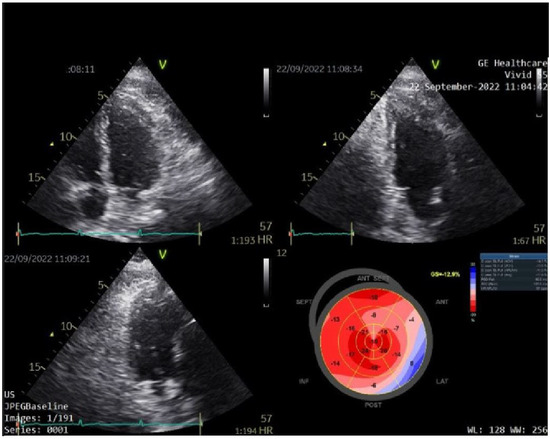

We used speckle-tracking echography in 4-3- and 2-chamber apical incidences to calculate the global LV strain, which was found to be significantly decreased (<12%, normal range > 20%). We then assessed the myocardial work (MW) of the patient. The LV-pressure strain loop (PSL) in this new method is derived from non-invasively acquired brachial artery cuff pressure and generated by adjusting the profile of a reference LV pressure curve according to the duration of the isovolumic and ejection phases, as defined by the echocardiography timing of aortic and mitral valve events. After calculating the global LV strain, measurements of brachial blood pressure and time of valvular events were utilized to obtain the LV-PSL with currently available echocardiographic software. The area of the PSL represents approximately the MW and is computed by multiplying the rate of segmental shortening, obtained by integrating the strain curve, by the momentary LV pressure. This product is a measure of instantaneous power, which is incorporated throughout the cardiac cycle to generate MW, which is given in mmHg%. In addition to the MW index (work assessed from mitral valve closure to mitral valve opening), segments were examined for wasted work (WW) and constructive work (CW), with global values calculated as the mean of all segmental values. The global myocardial work index (1123 mmHg%; normal value > 1200 mmHg%), which measures LV work during systole, was reduced. As shown in Figure 3, myocardial work efficiency, which is calculated as the ratio of constructive to wasted work, was also found to be lower (85%, normal value > 90%).

On the polar map of the GLS, the regions with the lowest longitudinal strains were the anterior, lateral, and posterior ones, with the smallest value being observed at the level of the anterior region (−4%), as shown in Figure 3A.

The polar map of the global MW index (Figure 3B) also showed that the anterior, lateral, and posterior regions of the LV wall present lower values of the MW index, the lowest value being observed at the level of the posterior area (447 mmHg%).

The echographic images suggested severe blood flow abnormalities in these regions, which are irrigated from branches originating from the circumflex and from the right coronary artery, as shown in Figure 4.

Figure 3. (A) Bull’s-eye polar map of left ventricular global longitudinal strain. (B) Myocardial work index, and efficiency.